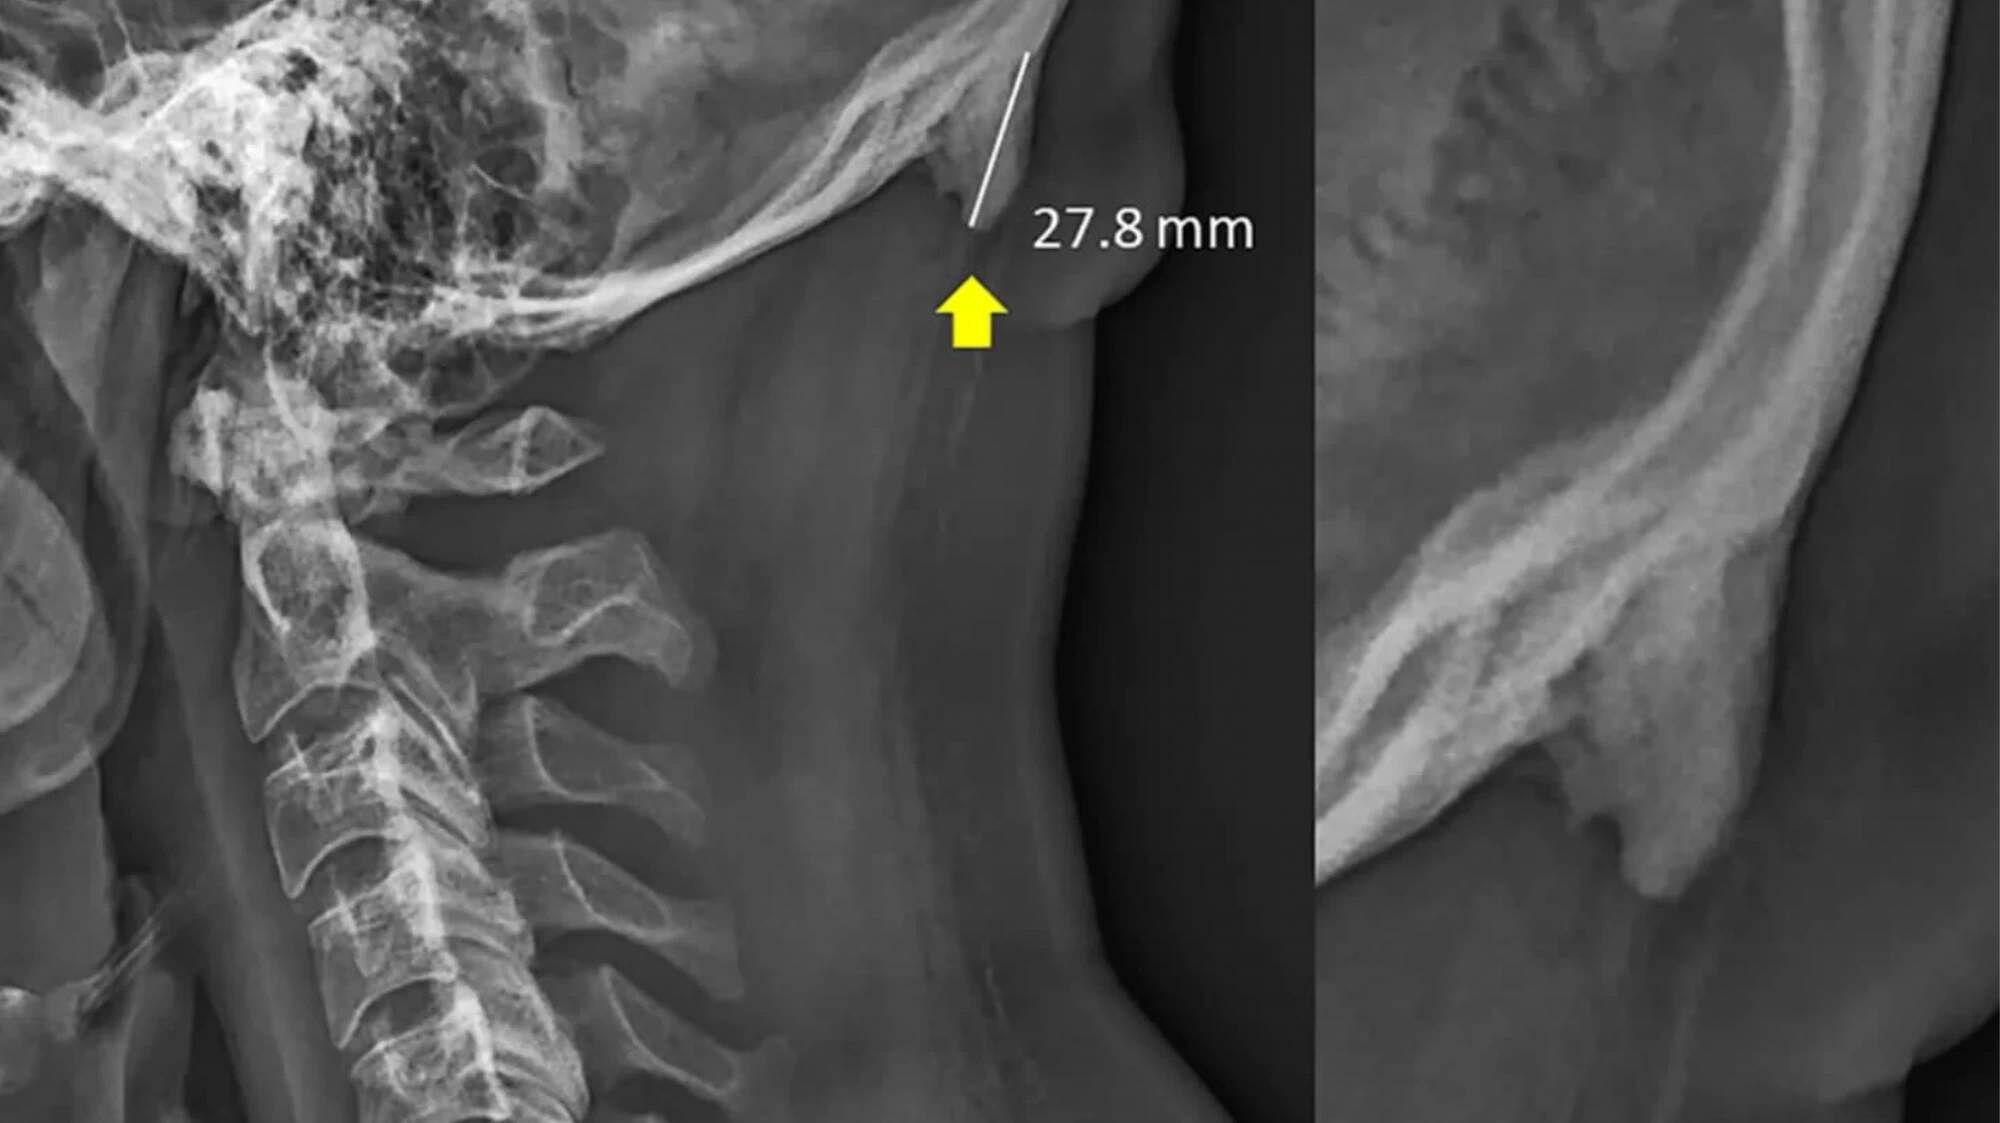

Egy Queenslandi egyetem két kutatója, David Sahar és Mark Sayers egy betegséget vizsgáltak, ami környezeti, kémiai és genetikai okok hatására kialakuló csontkinövésekkel jár a koponyán. A tanulmányban azt mutatták ki, a fiatalok nagyobb eséllyel tapasztalják a jelenséget, mint a harminc éven felüliek.

Az eredeti, 2016-ban megjelent tanulmány összesen 218, 18 és 30 év közötti alanyt vizsgált, 41 százalékuk rendelkezik kisebb csontkinövéssel a koponyájuk hátulján. A kutatók azt feltételezik, ezt az arányt a megnövekedett gyerekkori mobiltelefonhasználat okozhatja.

Azonban fontos kiemelni, hogy ez csupán spekuláció. A tanulmány nem mérte a telefonhasználatot, kizárólag az alanyok korára és a ritka betegség arányára reflektál.

A tanulmányt 2018-ban folytatták, négy, 13 és 16 év közötti, csontkinövéses fiút vizsgálva nem találtak kapcsolatot a genetika és a betegség között. A telefonhasználattal sem kapcsolták össze a jelenséget.

Többen kiemelték, hogy a tanulmány több helyen ellentmondásos. Egyszer egy grafikont látunk, amely szerint férfiak kisebb arányban szenvednek a betegségben, azonban a szöveg az ellenkezőjét állítja. Ezen kívül pedig a vizsgált korcsoport is inkonzisztens, egyszer 18 és 29 közötti, később 18 és 30 közötti alanyokat említ.

Tehát nehéz lenne azt állítani, hogy ez a tanulmány megbízható, és a telefonhasználat hatására szarvunk nőhetne.